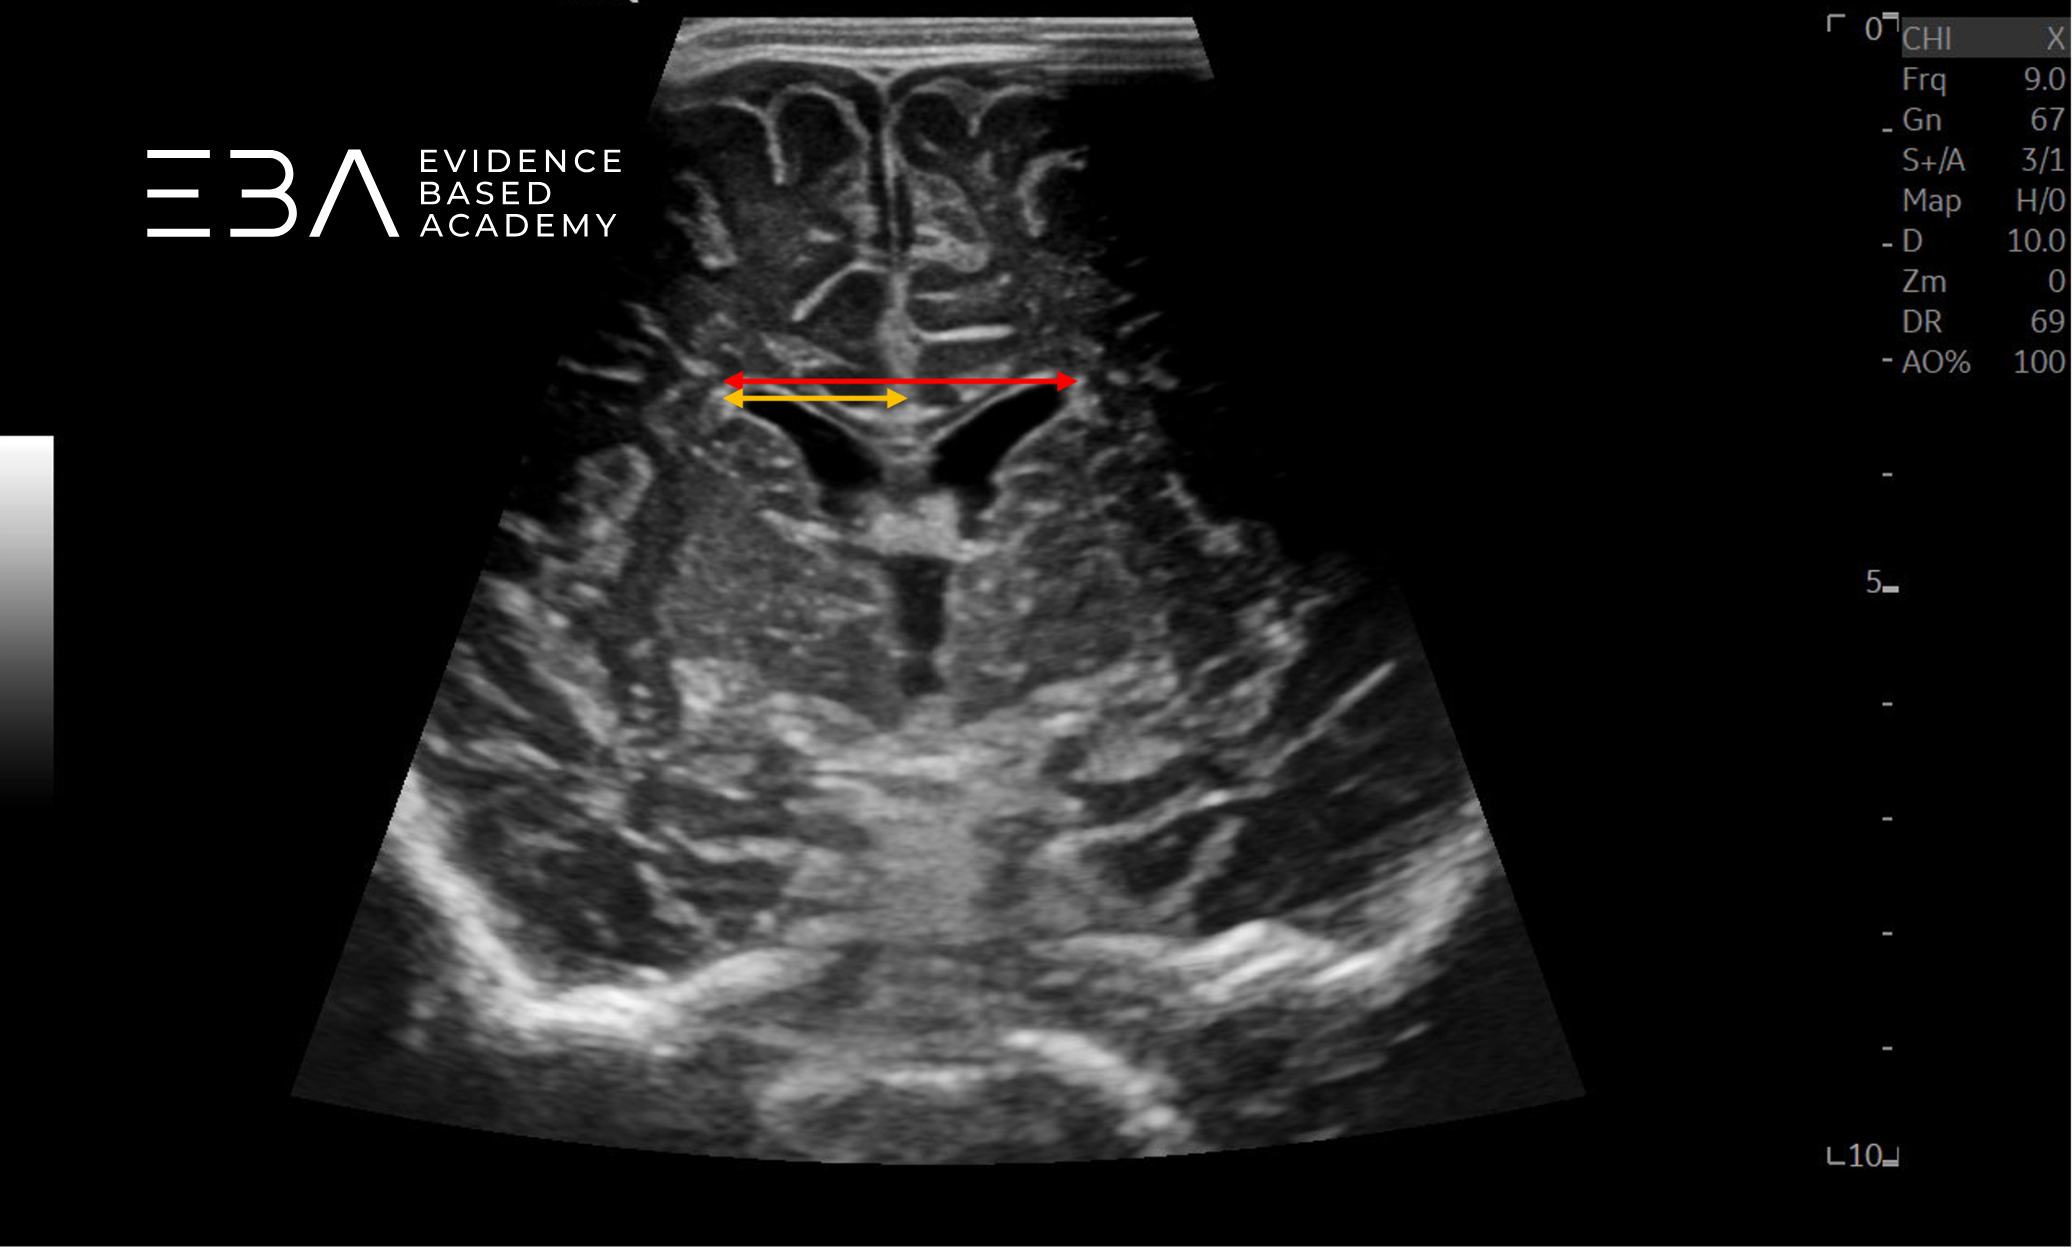

zdj. c

Głowica liniowa. Czerwoną strzałką zaznaczono pomiar rozpiętości rogów czołowych komór bocznych, żółtą strzałką zaznaczono wskaźnik komorowy.

zdj. e

Głowica liniowa. Czerwoną strzałką zaznaczono pomiar rozpiętości rogów czołowych komór bocznych, żółtymi strzałkami zaznaczono pomiar szerokości rogów przednich.